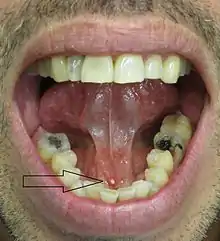

Signs and symptoms are variable and depend largely upon whether the obstruction of the duct is complete or partial, and how much resultant pressure is created within the gland.[1] The development of infection in the gland also influences the signs and symptoms.

- Pain, which is intermittent, and may suddenly get worse before mealtimes, and then slowly get better (partial obstruction).[3]

- Swelling of the gland, also usually intermittent, often suddenly appearing or increasing before mealtimes, and then slowly going down (partial obstruction).[3]

- Tenderness of the involved gland.[3]

- Palpable hard lump, if the stone is located near the end of the duct.[1][3] If the stone is near the submandibular duct orifice, the lump may be felt under the tongue.

- Lack of saliva coming from the duct (total obstruction).[3]

- Erythema (redness) of the floor of the mouth (infection).[3]

- Pus discharging from the duct (infection).[3]

- Cervical lymphadenitis (infection).[3]

- Bad breath.[3]

Rarely, when stones form in the minor salivary glands, there is usually only slight local swelling in the form of a small nodule and tenderness.[1]